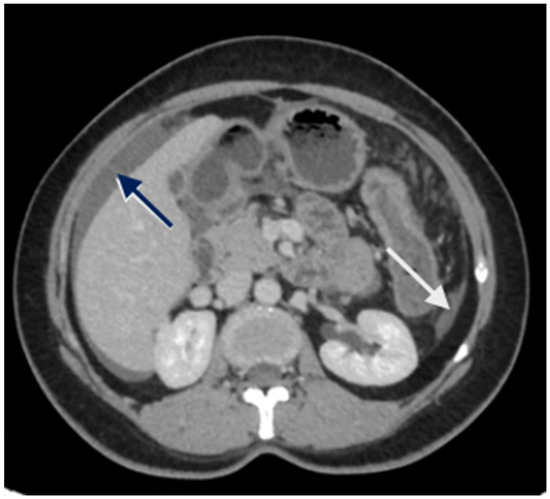

5. Preoperative Imaging